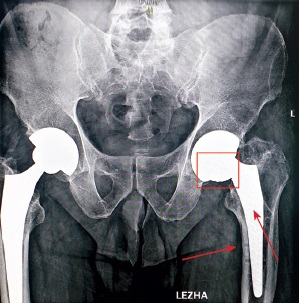

Sequential X-ray methods of research using plain pelvic radiography in the antero-posterior view revealed a satisfactory inclination of the acetabular component, a varus position of the femoral component of 10°, and a distortion of the endoprosthesis contours in the lower region of the acetabular component and the femoral neck component, which was regarded as a fracture of the ceramic liner or head that make up the bearings. Signs of a previously installed DHS surgical hardware, as well as channels from previously inserted cortical and dynamic screws, were visualized in the cortical area in the upper third of the diaphysis of the left femoral bone after removal in the diaphyseal and subtrochanteric regions (Fig. 1, 2).

Fig. 2. Overview X-ray of the hip joints with full femoral capture. On the left is a 10° varus placement of the femoral component